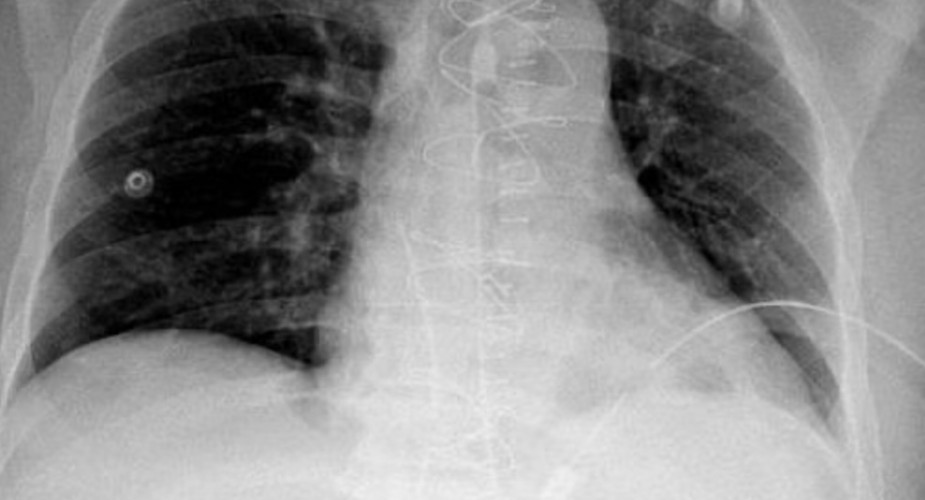

وأكدت الأشعة الصوتية وجود تجمع دموي حول القلب في تجويف التامور مع وجود استرواح هوائي حول الرئة اليسرى، ليتم نقله مباشرة إلى غرفة العمليات بواسطة الفريق الطبي المكون من استشاري الإصابات د. زيسس تولوميس، وزميل جراحة الإصابات د. أحمد فلاتة، وأخصائي الجراحة العامة د. أسرار الوادعي، ويترأسها استشاري ورئيس مركز الإصابات د. شرف الدين شودري.

وتم فتح صدر المريض من خلال عظمة القص، وتحرير القلب من الضغط المتكون من تجمع الدم في تجويف التامور، بعد ذلك تم التحكم بالنزيف وإصلاح عضلة القلب، وبتوفيق الله تحسن المريض وغادر العناية المركزة بعد يومين وهو بصحة جيدة.